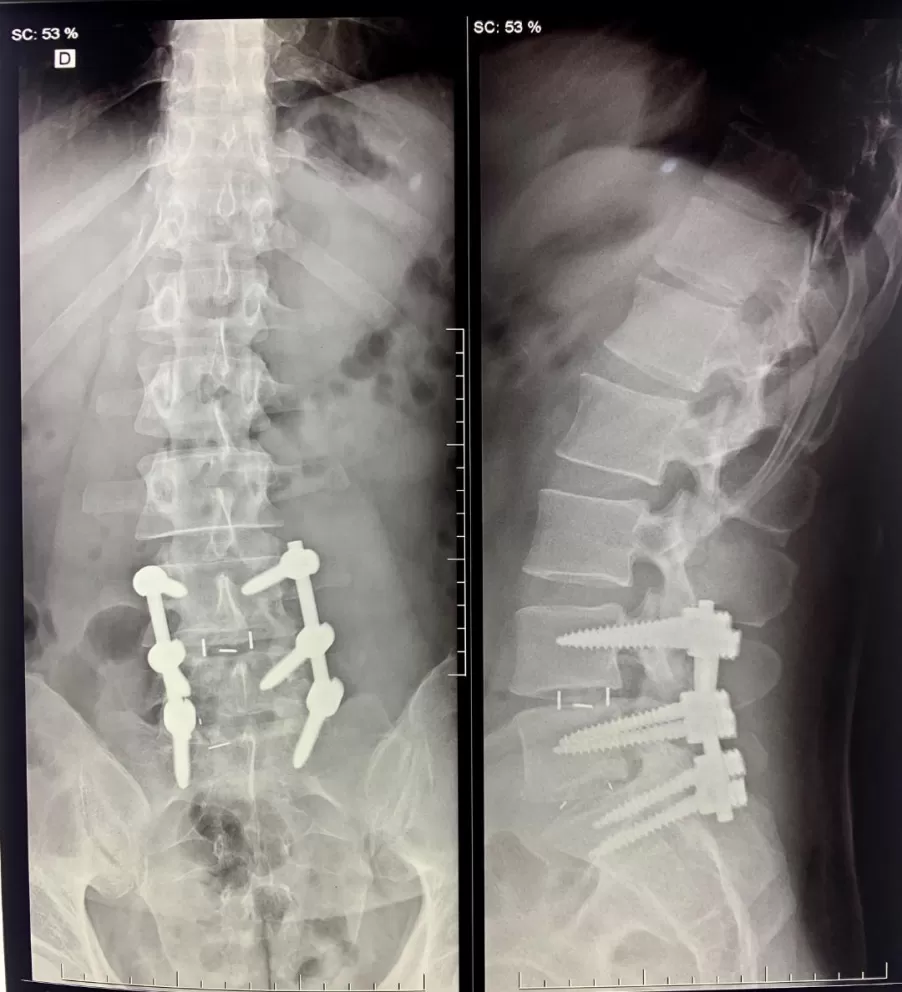

O bloqueio ou infiltração de Coluna é um procedimento realizado para tratar as doenças que acometem a Coluna Vertebral, em toda a sua extensão, desde a região cervical, dorsal, lombar, até o sacro e cóccix. Para esse procedimento é utilizado algum equipamento de imagem que serve como guia para auxiliar a injeção da medicação. Na clínica é utilizado o aparelho de Ultrassonografia. É uma técnica simples que exige apenas anestesia local da pele.

Como é feito o bloqueio de Coluna no consultório?

O procedimento é realizado apenas com anestesia local da pele, que evita que o paciente sinta dor. Em todo o tempo, o procedimento é guiado pelo Ultra-som e o paciente pode retornar às suas atividades no dia seguinte.